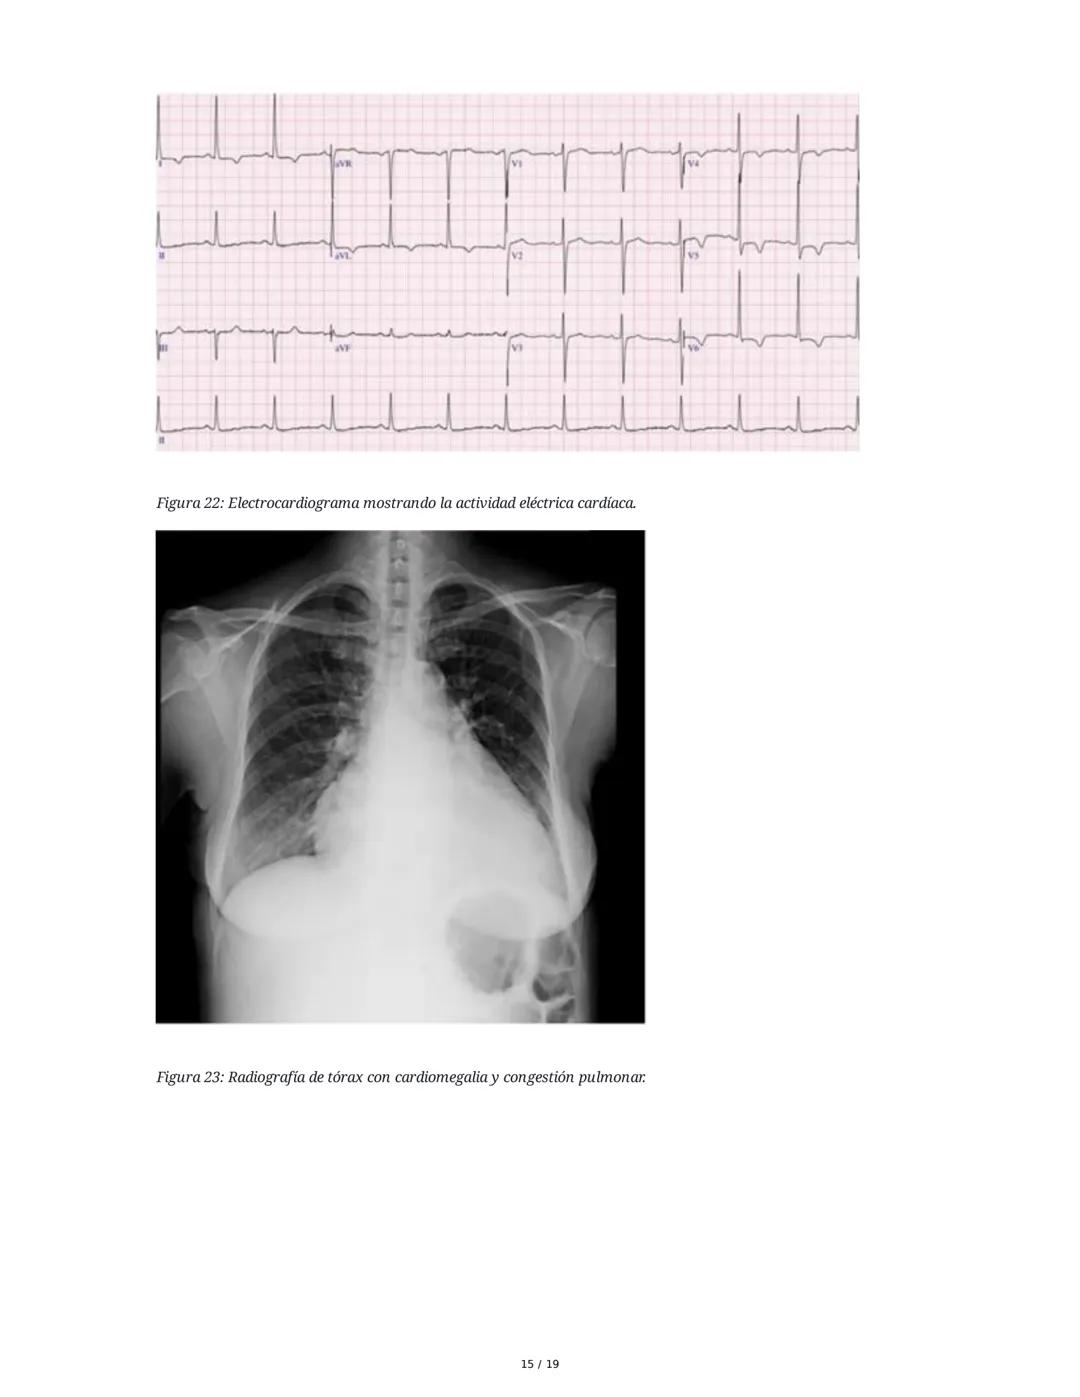

Los signos de falla izquierda incluyen llenado capilar lento, piel fría, palidez, cianosis y crépitos pulmonares. En la falla derecha encontramos ingurgitación yugular, hepatomegalia, ascitis, derrame pleural y edema maleolar.

Los Criterios de Framingham facilitan el diagnóstico: se requieren 2 criterios mayores o 1 mayor más 2 menores para confirmar IC. Entre los criterios mayores están la disnea paroxística nocturna, distensión yugular, crepitaciones pulmonares y cardiomegalia.